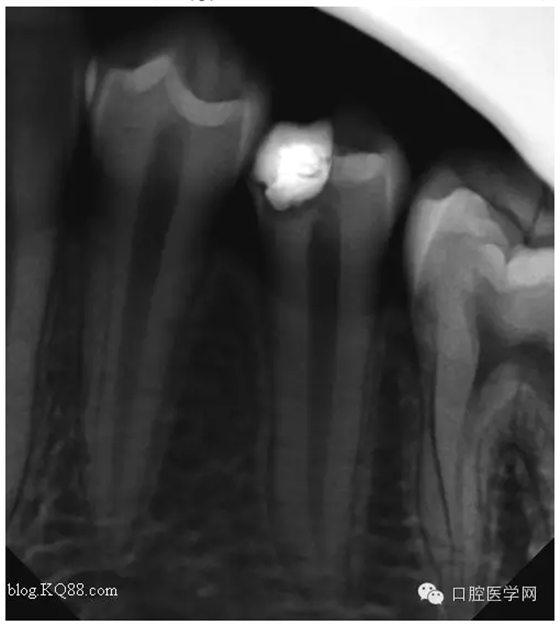

一月后復(fù)查:高聳的髓角變鈍,形成約0.5mm修復(fù)性牙本質(zhì)?;佳罒o癥狀。牙髓活力測試同對照牙。

兩月后復(fù)查:高聳的髓角變的更鈍。遠中髓壁形成較厚的修復(fù)性牙本質(zhì)。溫度測試同對照牙。